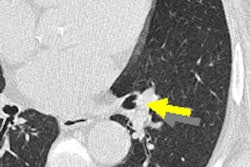

"CAD detected many more nodules compared to visual detection ... and agreement was only fair between the two methods," Silva said. "Most interestingly, CAD detected many more part-solid nodules that are associated with more clinically relevant disease, meaning cancer. A few part-solid nodules were seen only in visual detection, and while the diameter was similar, the volume was different. CAD detected smaller nodules."

CAD detected smaller nodules than the human readers. Images courtesy of Dr. Mario Silva.Visually detected nodules were smaller in mass, suggesting they were a bit fainter than the CAD-detected nodules. CAD missed some as well.